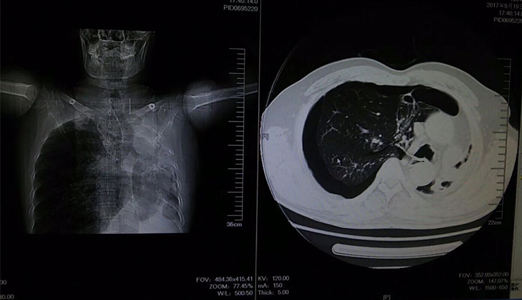

9月19日,临床医学院/附属医院急诊科成功抢救了一例急危张力性气胸患者,急诊抢救的快速反应及多学科协作的科学规范获患者及家属好评。现患者病情稳定,已转入胸外科进一步治疗。

该患者为中年男性,胸闷,气促,休息后症状无缓解,来院就诊时全身大汗淋漓,口唇发紫,呼吸困难。临床医学院/附属医院医生询问病史后,发现该患者病情较复杂,且患者及家属对既往病史情况不太了解。考虑情况危急,当班医师立即组织抢救,给予吸氧、建立静脉通路及行胸部CT,同时请胸外科医师急会诊。经详细检查后,发现患者右肺自发性气胸,如不及时救治将危及生命。医务人员立即为患者做了右胸腔穿刺排气抢救,后给予胸腔闭式引流。在全体医护人员一个多小时的努力下,患者病情得到缓解,患者及家属对临床医学院/附属医院医务人员的精湛医术表示感谢。